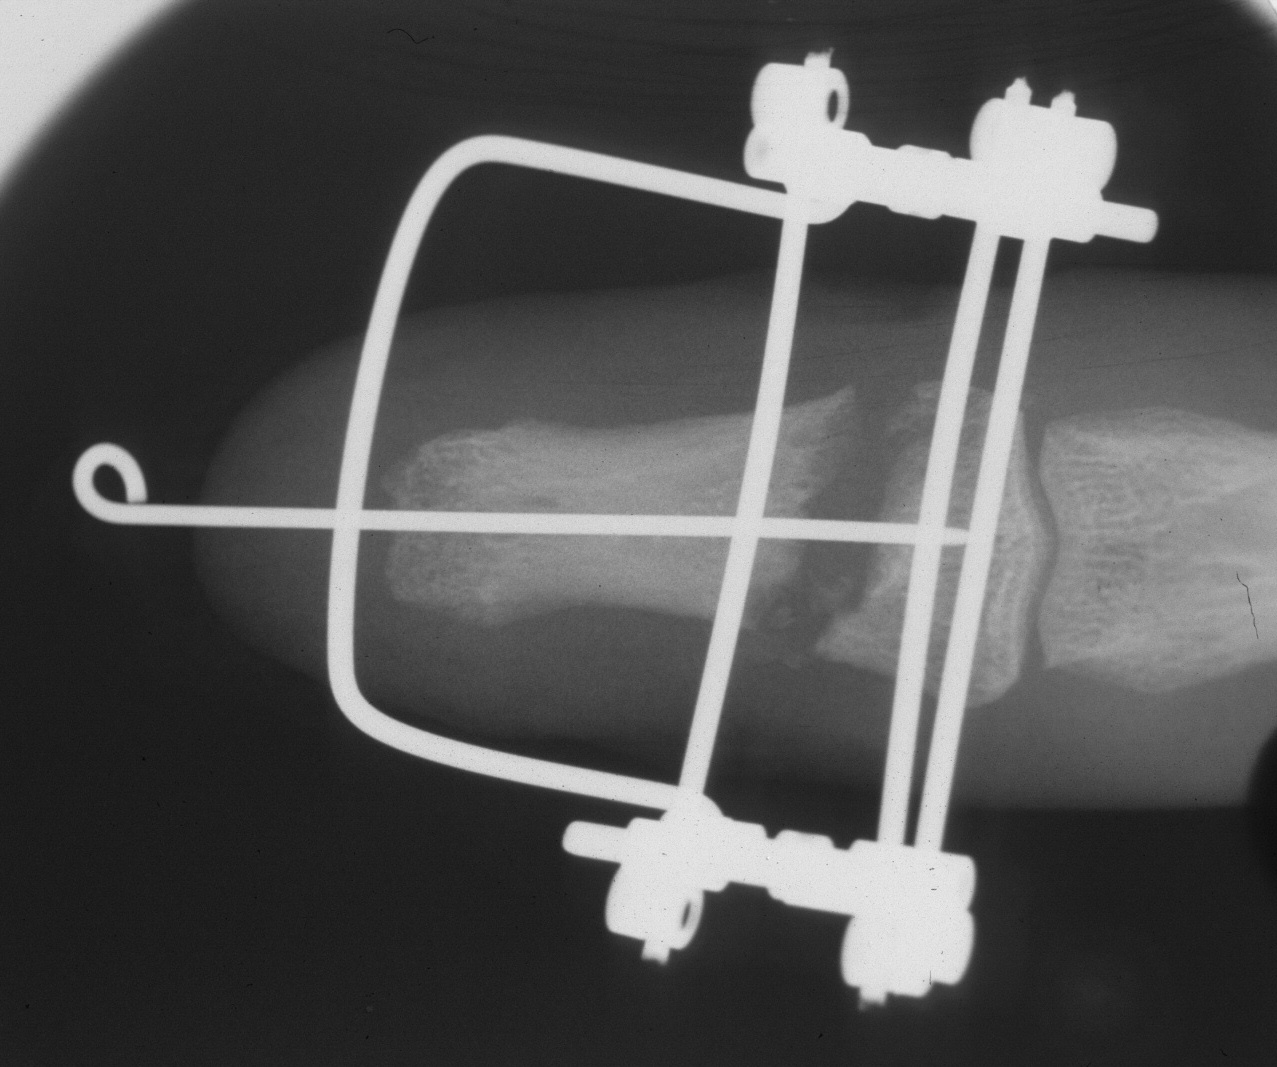

A palatal expansion clamp with a turnbuckle mechanism was used to design a progressively lengthening external fixator to restore length of the distal phalanx before reconstruction with a bone graft, here shown on a plastic sawbone model. This device is available at http://www.greatlakesortho.com and other orthodontic supplier retailers (no commercial interest).

Construction of the fixator:

Initial position:

After two weeks of distraction: